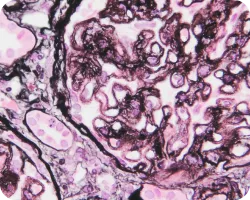

Сегментарный гломерулосклероз (более четырех мезангиальных клеток):

Image

Сегментарный гломерулосклероз

Признаки гипертрофии подоцитов или склероз с локализацией на канальцевом полюсе, являющиеся одной из причин сегментарного гломерулосклероза, связаны с более выраженной протеинурией и более быстрым снижением функции почек. Вместе с тем у пациентов, имеющих описанные признаки, иммуносупрессивная терапия связана с лучшей почечной выживаемостью22.